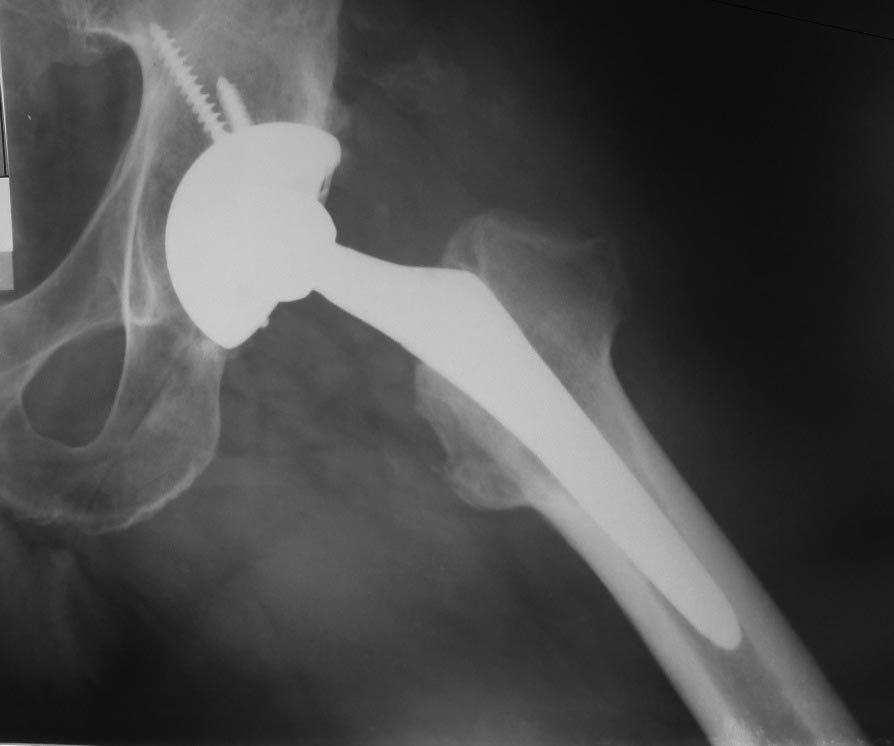

Уважаемые коллеги. В сообщении от 02 июля 2013 г. я уже писал об этом случае. Эндопротезирование пациенту 49 лет выполнил в 2007 г. по поводу коксартроза. В начале мая 2013 г. в состоянии запоя он упал со скамейки, после чего отметил припухлость в области паха и левой ягодицы. За помощью обратился почти через 2 мес. При пункции было удалено около 200 мл стерильной гноеподобной жидкости из области эндопротеза. За несколько дней жидкость снова набралась. 04.07.13 произведена санация гнойной полости с последующим вакуумированием раны. Во время операции признаков нестабильности и износа компонентов протеза, а также дебриса выявлено не было. Заменить полиэтиленовый вкладыш не удалось из-за неисправного запорного механизма. 08.07.13 выполнена пластика раны местными тканями. Дренаж удален через день. На фоне гладкого послеоперационного периода, 17.07.13, вследствие нарушения режима, произошел вывих головки эндопротеза, вправленный в тот же день закрыто. Послеоперационная рана зажила первичным натяжением, выписан 29.07 с рекомендацией ходить в ортезе при помощи костылей с частичной нагрузкой на левую ногу до 1 мес. после вывиха эндопротеза. Через неделю снова «ушел в запой» и был госпитализирован с очередным вывихом протеза. Подобные эпизоды повторялись до декабря 2013 г. еще 5 раз. Каждый раз удалялось до 100 мл стерильной серозногеморрагической жидкости. При последней госпитализации была отмечена гиперемия дистальной 1/3 послеоперационного рубца. Впоследствии пациенту удалось победить порочное пристрастие. Сейчас работает по специальности (водитель), при длительной ходьбе и к концу рабочего дня отмечает дискомфорт или легкую болезненность в области тазобедренного сустава. Наблюдаю его с интервалом в 2-3 месяца. Каждый раз пунктирую область эндопротеза, последние 2 раза жидкости практически не было. СОЭ – 25-40, С-рб до 15-20. Мыслей о замене протеза сейчас нет. Последние (июньские) рентгенограммы – без особенностей (прилагаются). Смущает только обширное синюшно-розовое пятно с отечной кожей (на фото), появившееся в декабре 13 г.: признаком чего оно может являться? Имеет ли прогностическую ценность? Встречался ли кто-нибудь с подобным? Заранее спасибо за ответы.